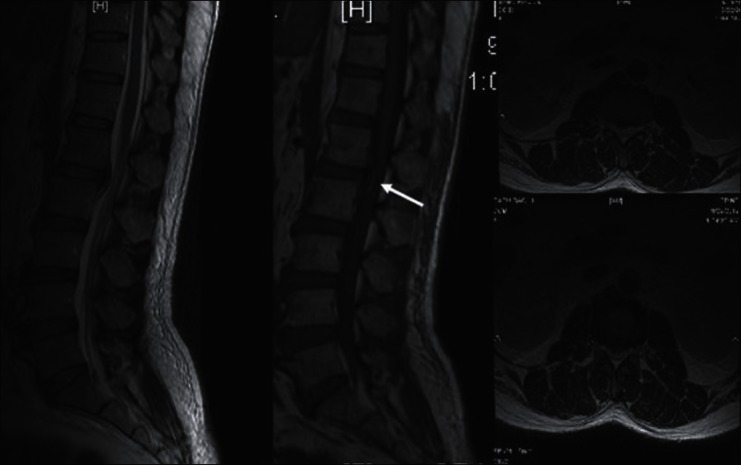

Sagittal and Axial MRI images of lumbar spine show elevated Posterior Longitudinal Ligament at D12-L1 level with evidence of hemorrhage (arrow). No significant cord signal changes are seen

A 50-year-old man presented to our emergency department with history of lightning strike when he was standing under a tree in the course of a lightning storm. He was unconscious for 15 min, and after he regained consciousness, he was unable to move both his lower limbs with loss of sensations and urinary retention. On examination, tone in both lower limbs was normal. He had grade 0 power in both lower limbs, with a sensory level up to D12. Reflexes were depressed and plantars were equivocal. There was a 30% loss in L1 dermatome downward, which was almost complete in S1 dermatome. On the 2nd day, his power improved to grade III bilaterally which improved to grade IV the very next day so that he was ambulant by now. X-rays were within normal limits. The Magnetic Resonance Imaging (MRI) brain was normal, while spine imaging showed the evidence of ruptured posterior longitudinal ligament (PLL) at D12–L1 level with evidence of hemorrhage [Figure 2]. This could also have been a result of trauma. However, no signal intensity changes were seen in the cord at that level. This patient later on developed ARF for which nephrology consultation was taken and he was transferred under their care.